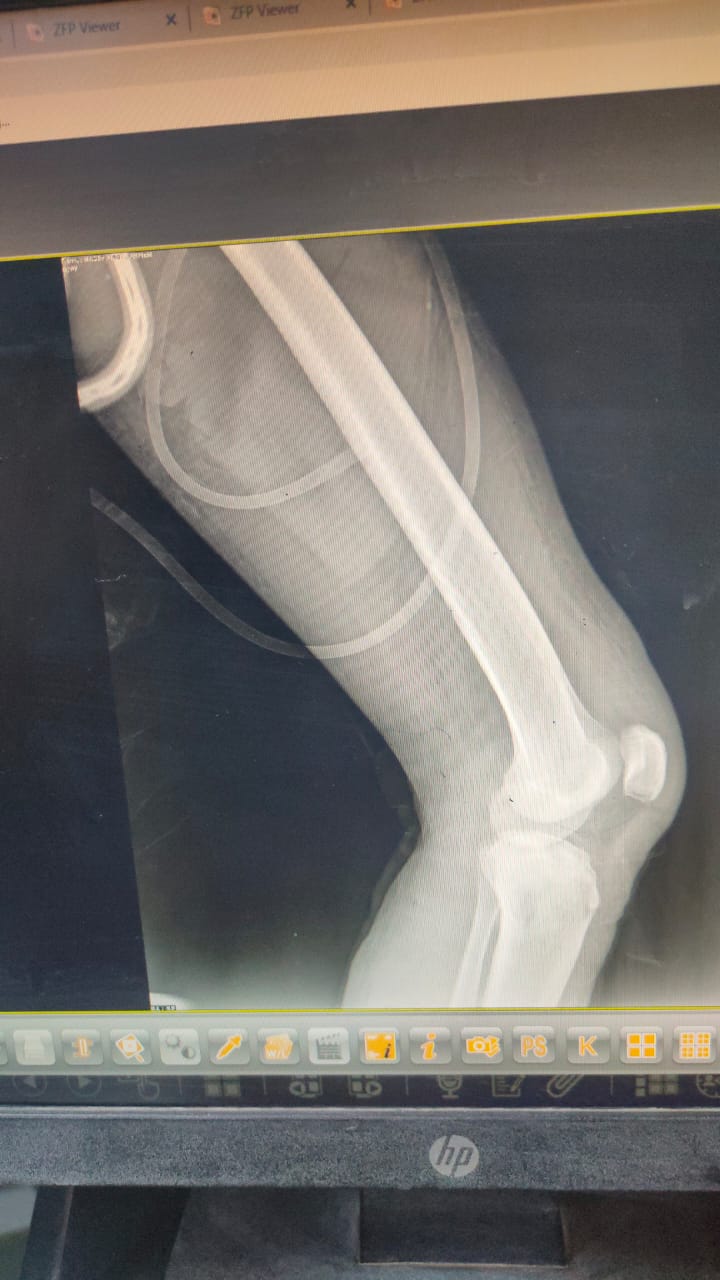

نجح فريق طبى مشترك من قسمى العظام وجراحة التجميل بمستشفى السنبلاوين العام في التدخل السريع لترقيع جلد الساق لمريض يعانى من كسرمضاعف بعد تركيب مثبت خارجي.

وأوضح الدكتور تامر مدكور وكيل الوزارة، أن الحالة تم تحويلها لمستشفى السنبلاوين وهى تعانى من كسر مضاعف مفتوح من الدرجة الثالثه بالساق اليسرى مع فقدان في الجلد والانسجة حيث تم تثبيت الكسر بمثبت خارجي مع الحفاظ على وضع الكسور ورد العظام وعقب ذلك جرى ترقيع للجلد من خلال أطباء جراحة التجميل.